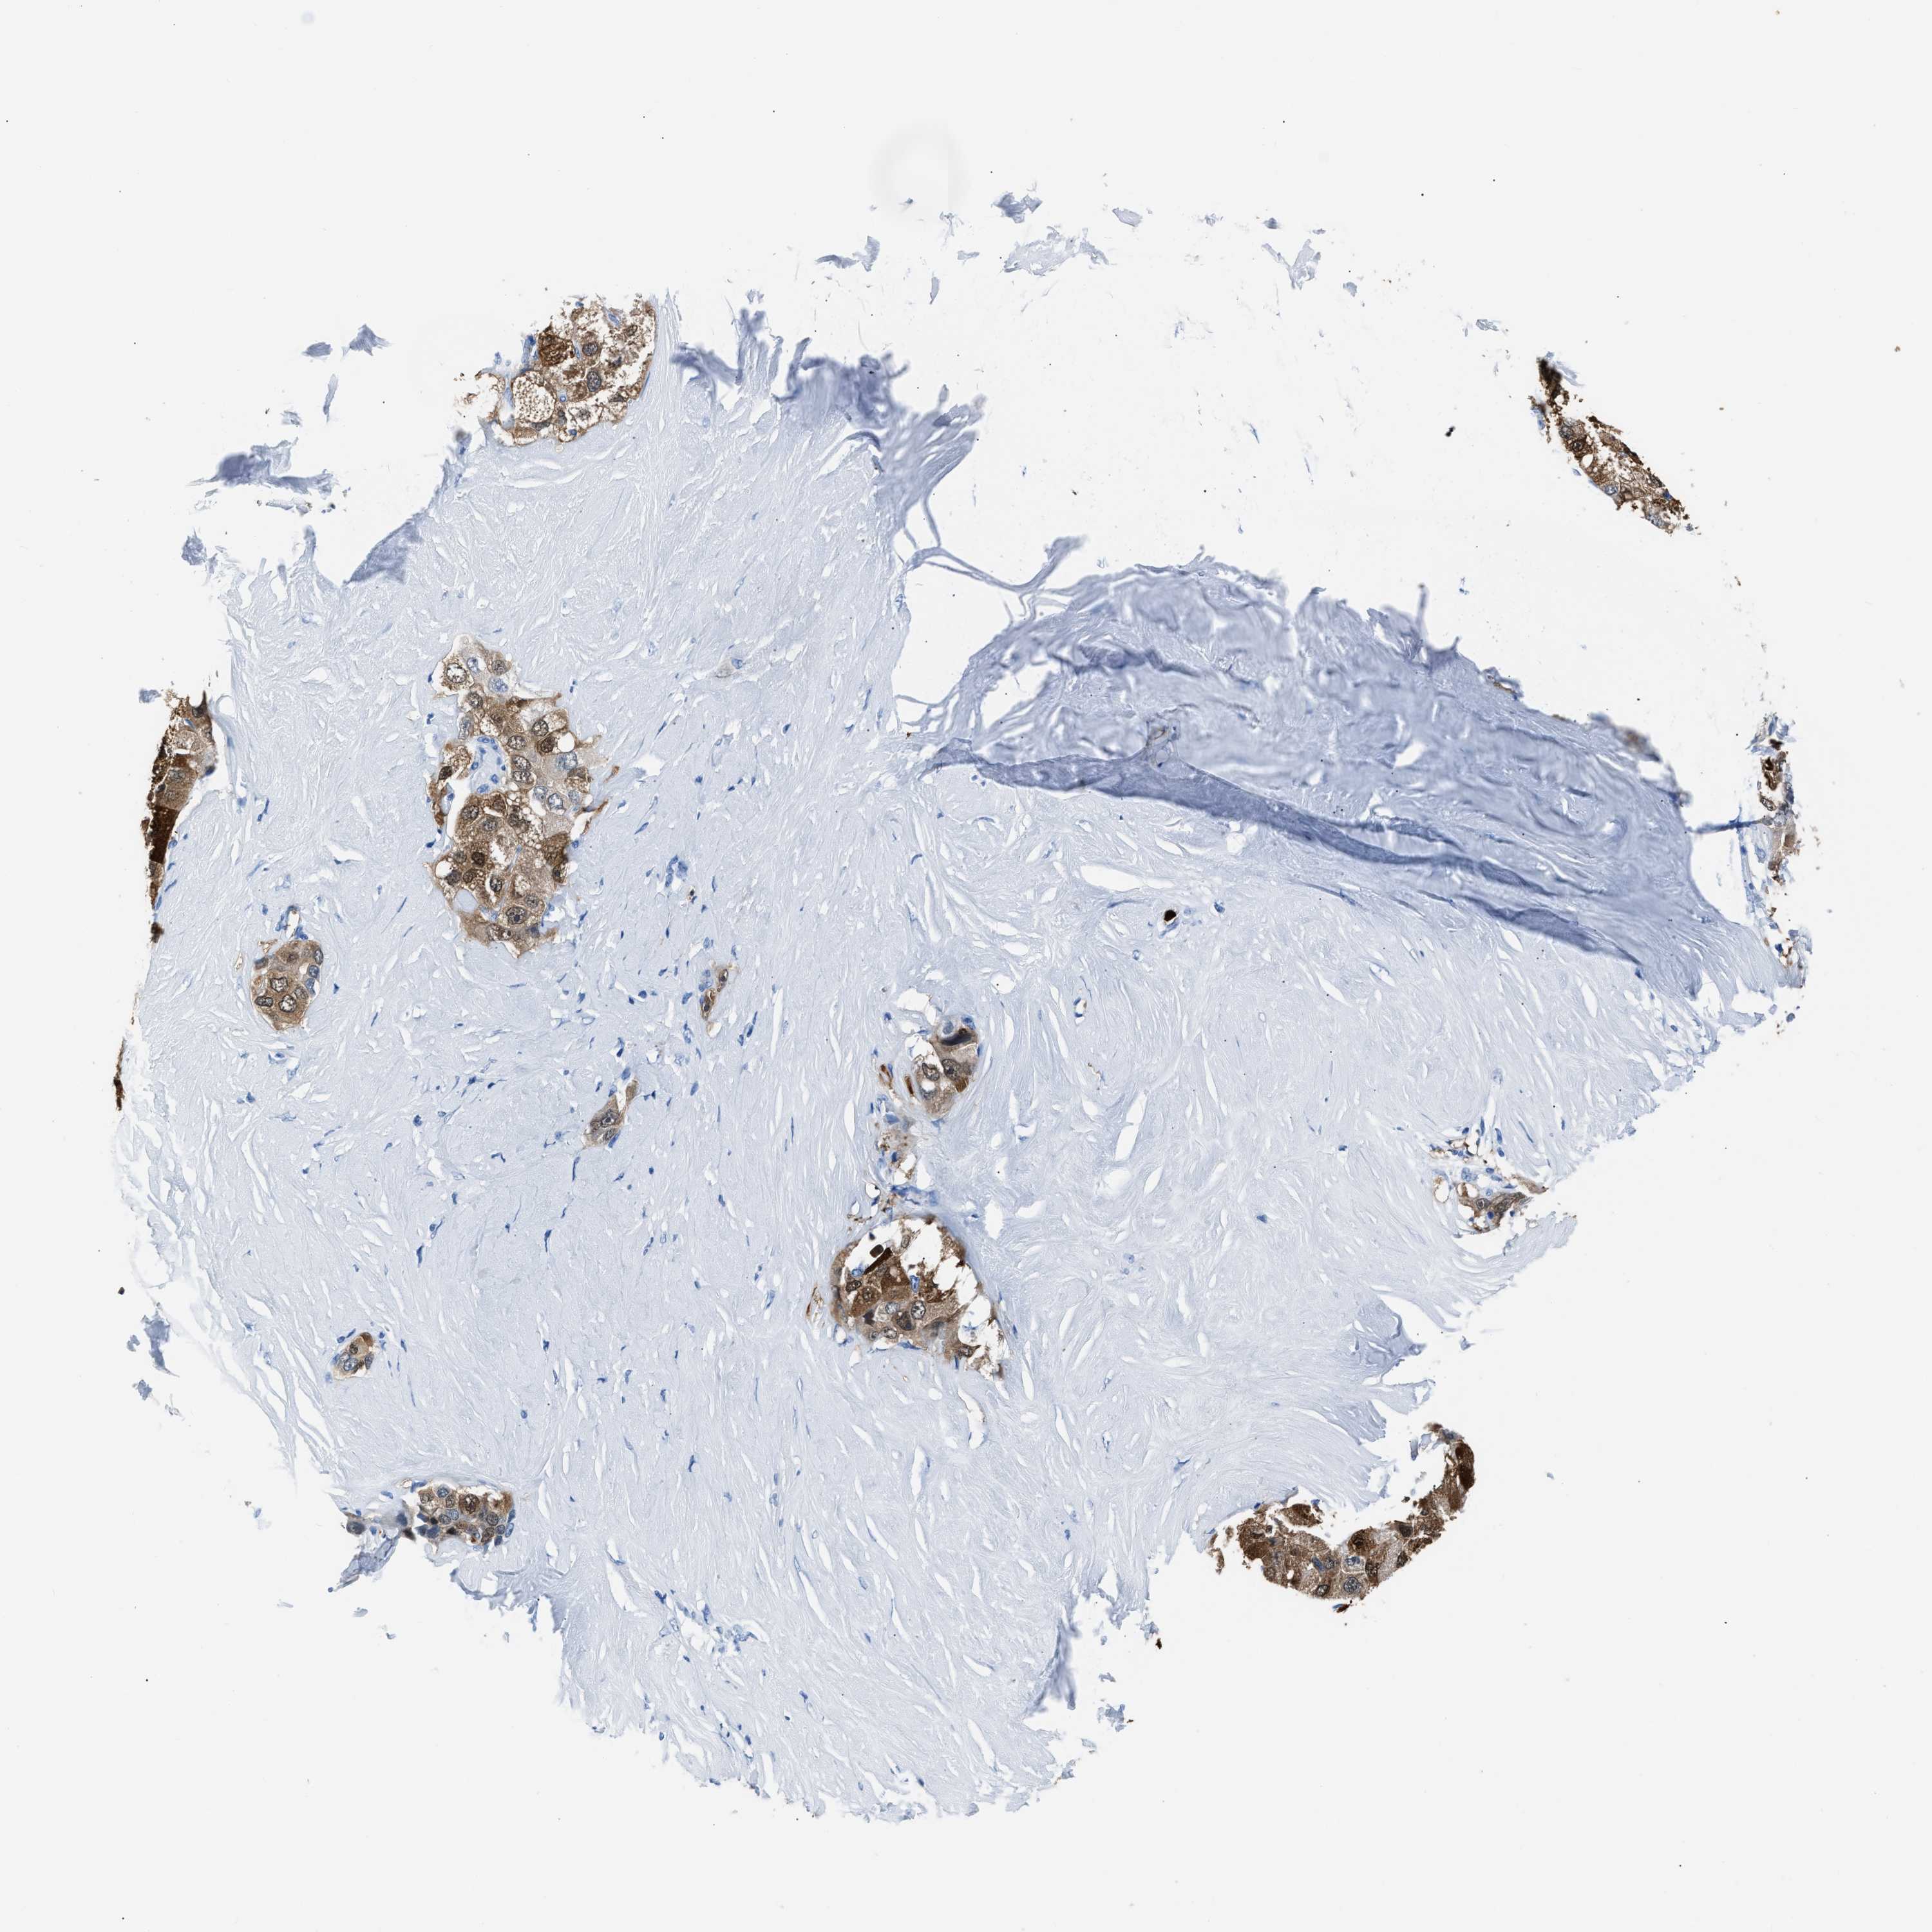

LIVER CANCER - Protein expressioni

A mouse-over function shows sample information and annotation data. Click on an image to view it in a full screen mode. Samples can be filtered based on level of antibody staining by selecting one or several of the following categories: high, medium, low and not detected. The assay and annotation is described here.

Note that samples used for immunohistochemistry by the Human Protein Atlas do not correspond to samples in the TCGA dataset.

Antibody stainingi

Antibody staining in the annotated cell types in the current human tissue is reported as not detected, low, medium, or high, based on conventional immunohistochemistry profiling in selected tissues. This score is based on the combination of the staining intensity and fraction of stained cells.

Each image is clickable and will lead to virtual microscopy that enables deeper exploration of all samples and also displays staining intensity scores, fraction scores and subcellular localization as well as patient and tissue information for each sample.

Antibody HPA019502

Staining

High

Medium

Low

Not detected

Intensity

Strong

Moderate

Weak

Negative

Quantity

>75%

75%-25%

<25%

None

Location

Nuclear

Cytoplasmic/membranous

Cytoplasmic/membranous,nuclear

Cholangiocarcinoma

Carcinoma, Hepatocellular, NOS